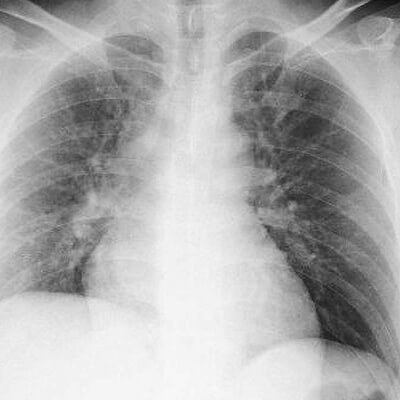

이는 혈관이 좁아지거나 갑작스럽게 혈전이 생기게 되면서 심장근육으로 가는 혈류가 완전히 차단된 현상을 말합니다. 심장은 사람이 살아감에 있어서 없어설 안될 존재이기에 잠시라도 멈추게 되면 심각한 상황에 직면할수 있습니다. 참고로 심장근육에 30분 이상 혈액이 공급되지 않으면 근육세포가 사멸하게 되어 심장펌프 기능이 현저히 떨어져 심부전으로 이어질 가능성이 높습니다.

심근경색은 천천히 진행되다가 어느순간에 돌입하면 인간이 느낄수 있는 최고의 가슴통증과 더불어 구토, 식은땀 등의 증상이 나타납니다. 처음부터 증상이 심각하지 않고 다른 사람보다 숨을 자주 헐떡이며 가슴이 답답하고 꽉막힌 느낌이 주기적으로 발생합니다. 그러다가 휴식시간이 되면 금방 안정화되어 심한 증상이 아닌것처럼 느껴집니다.